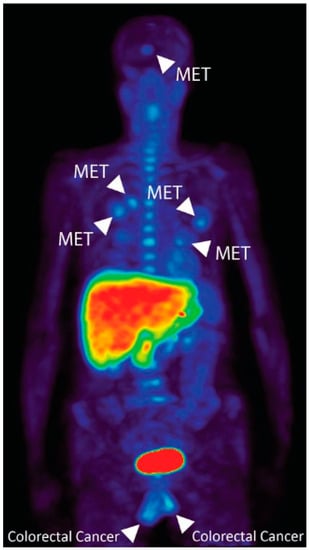

- Cohen, A.S.; Grudzinski, J.; Smith, G.T.; Peterson, T.E.; Whisenant, J.G.; Hickman, T.L.; Ciombor, K.K.; Cardin, D.; Eng, C.; Goff, L.W.; et al. First-in-Human PET Imaging and Estimated Radiation Dosimetry of [11C]-Glutamine in Patients with Metastatic Colorectal Cancer. J. Nucl. Med. 2022, 63, 36–43. [Google Scholar] [CrossRef]